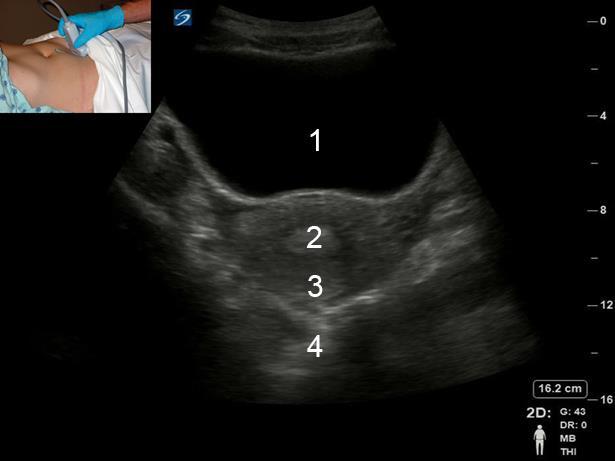

盆腔经腹 (TA) 横切面子宫图像

膀胱

子宫内膜

子宫

后盲囊